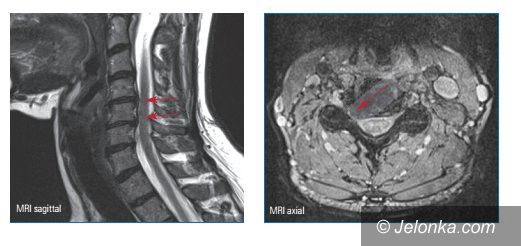

Nowoczesne leczenie małoinwazyjne dyskopatii szyjnej kręgosłupa w KCM

Fot. KCM Clinic SA